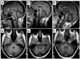

Naguib-Richieri-Costa syndrome